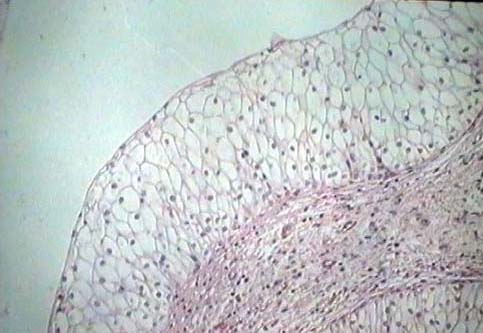

Niere und ableitende

Harnwege

Weiblicher Genitaltrakt